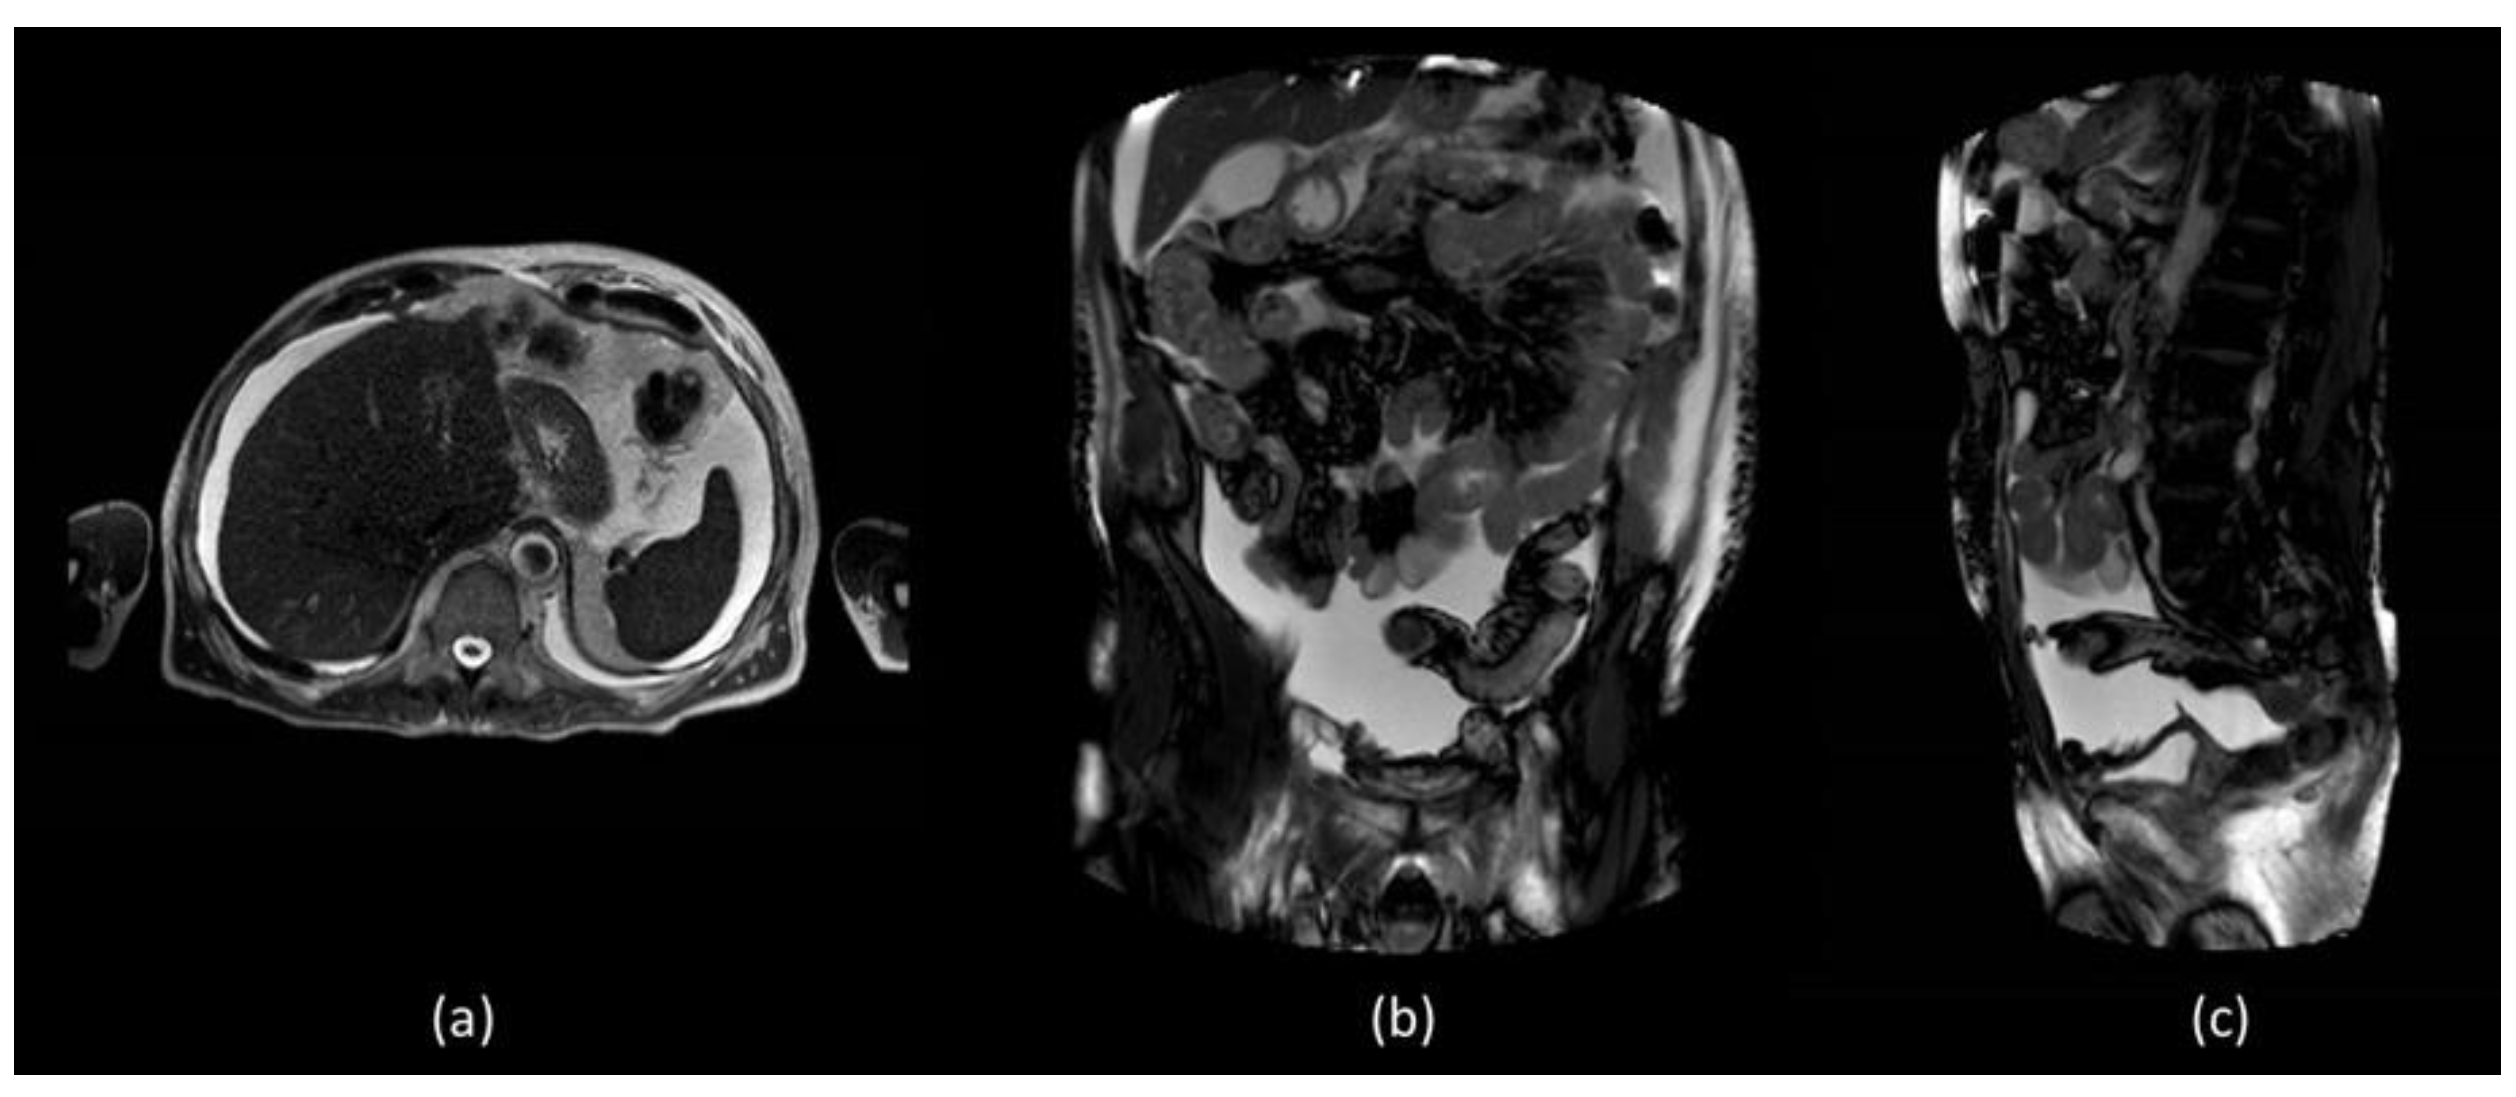

Unfortunately, he was readmitted 7 days later with abdominal distension and dyspnoea. During hospitalization, thorax and abdominal contrast-enhanced CT was performed which confirmed a massive ascites and described the presence of left pleural effusion without the presence of liver diseases (Figure 1).

Coronal (a) and sagittal (b) abdominal CECT showed massive ascites in supra and inframesocolic recesses. Non-hepatic diseases were recorded. (c) Sagittal thorax CECT demonstrated left pleural effusion.

In order to better assess the post-surgery pelvic region, abdominal MR was performed which did not show evidence of surgical injuries and liver diseases (Figure 2).

MR T1 weighted (a) axial section of the liver did not show diseases but confirmed the presence of massive fluid effusion, visible in the supra and submesocholic space and also in the coronal (b) and sagittal images (c).